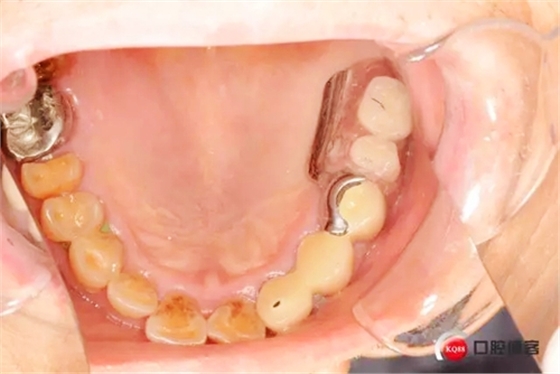

患者初診口腔情況15號(hào)牙為原做可摘局部義齒做卡環(huán)預(yù)備,真“專家”的活

1498573426_589043.jpg